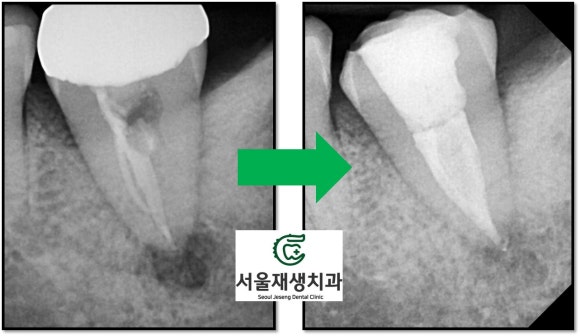

치료 전 후 사진을 비교해볼까요?

뿌리 속은 더욱 철저히 청소되었고,

뿌리 끝의 염증의 크기 또한

크게 감소했습니다.